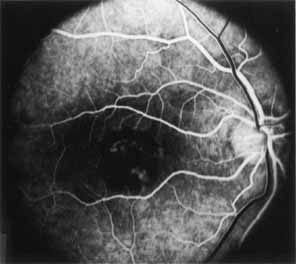

Although there is no reported genetic heterogeneity, there is wide phenotypic variation within the disorder. The major finding within the macula is a classic radial cystic maculopathy. Although retinal signs have been described in infants as young as 3 months, foveal schisis may be difficult to detect, leading to underdiagnosis. The diagnosis is usually not made until the affected male reaches school age (4 to 8 years of age) and encounters visual problems secondary to foveal involvement. Typical foveal schisis findings have been reported in 68% to 100% of eyes within various series.37,38 Foveal schisis is the only finding in about half the cases. It is characterized by the presence of radiate perifoveal microcysts located in the nerve fiber layer (Fig. 1) with radiate plications of the overlying internal limiting membrane that are seen especially well on monochromatic (red-free) photography (Fig. 2). The microcystoid change may slowly progress to form a macular cyst or hole. Foveal schisis has been reported in association with Goldmann-Favre vitreotapetoretinal dystrophy and rarely may be seen in rod-cone dystrophy or as an autosomal dominant or recessive condition.39–43